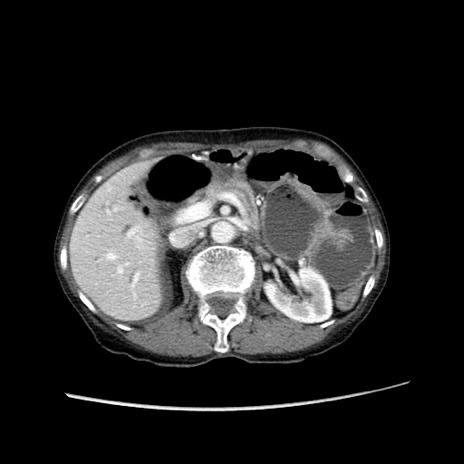

冠状断像

【症例】80歳代女性

【主訴】胸のつかえ感

【現病歴】約9時間前に食後から胸のつかえた感じあり、嘔吐あり、来院。

【既往歴】胃癌(全摘)、胆摘、虫垂炎

【身体所見】心窩部に圧痛あり、反跳痛なし。

【データ】WBC 5700、CRP 0.05